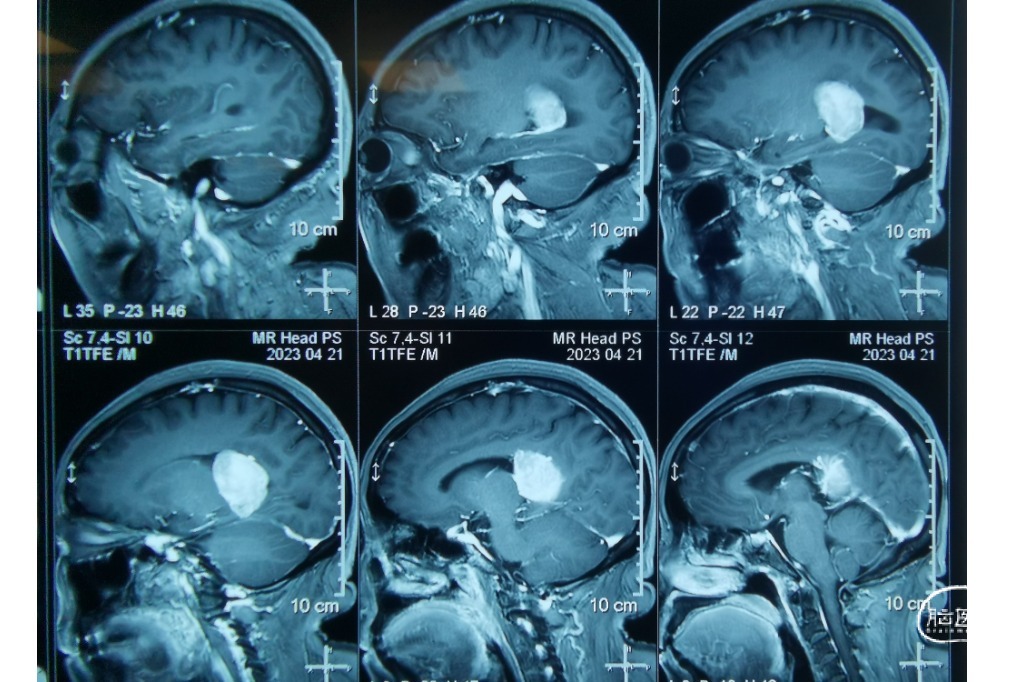

患者 女,66岁,因“头晕5年加重10天”入院。

患者头晕5年加重10天。

外院影像考虑脑膜瘤?室管膜瘤?

诊断:1.颅内占位性病变(左侧侧脑室三角区,脑膜瘤)2.高血压

2023.04.21外院MR